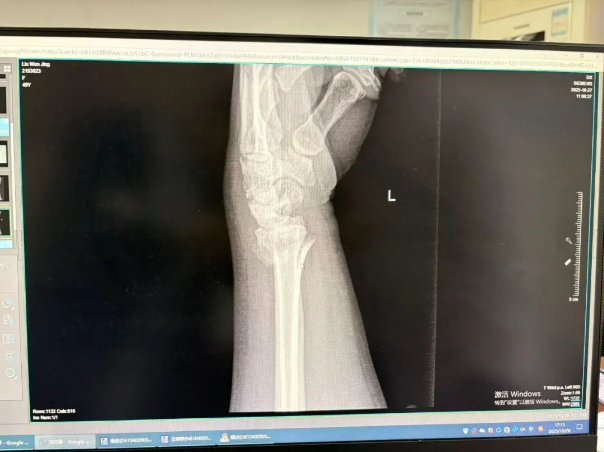

(骨折图示)

如果骨折是稳定的、没有明显移位的(比如青枝骨折),或者经过手法复位后对位良好、非常稳定的—— 我会优先考虑小夹板。 它的“动静结合”理念能让你在康复早期就开始活动,最大程度保留功能,体验感更好,恢复更快。

如果骨折是粉碎的、不稳定的、或者复位后容易再移位的 —— 那我必须请出石膏这位“镇山太保”。 此时,坚固的固定是第一要务,必须先确保骨头在一个良好的位置上长起来。